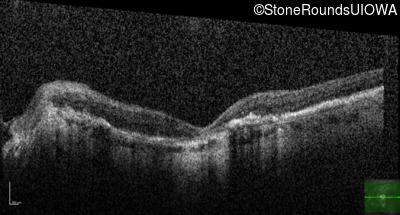

Optical Coherence Tomography - Right - 20/160 -2

Exemplar / OCT Stack